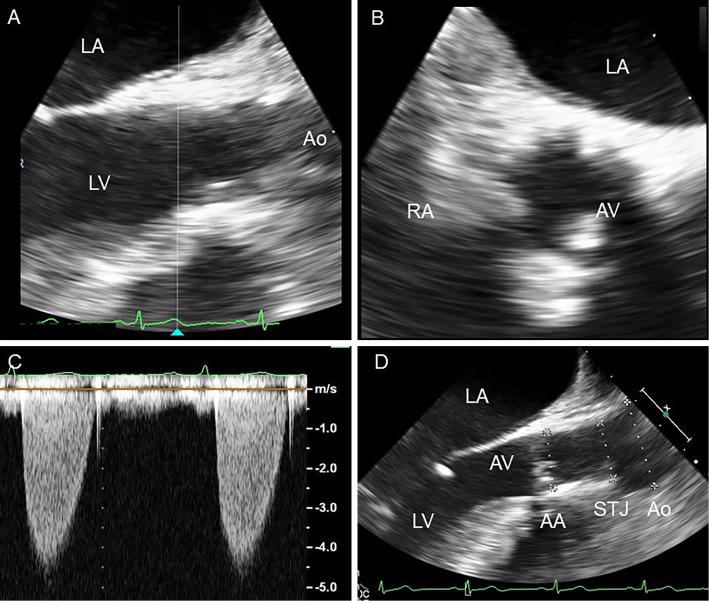

Two Cases of Surgical Management of Supravalvular Aortic Stenosis in Familial Hypercholesterolemia.

Ann Thorac Surg. 2018 Apr;105(4):e171-e174. doi: 10.1016/j.athoracsur.2017.11.025.